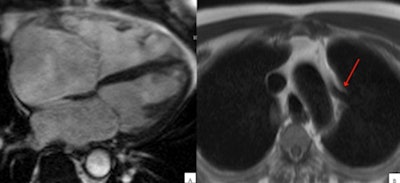

However, 11 patients or 9% had conditions that mimicked ARVC/D, including:

- Congenital absence of pericardium

- Asymmetric pectus excavatum

- Atrial septal defect with left or right shunting

- Arrythmogenic left ventricular cardiomyopathy

- Athletic heart (two)

- Left ventricular noncompaction cardiomyopathy

- Sarcoidosis

"CMR plays an important role in patients with suspected ARVC/D," Amadu said. Importantly, it can identify conditions that mimic the disease, representing 9% of the population studied, he added.